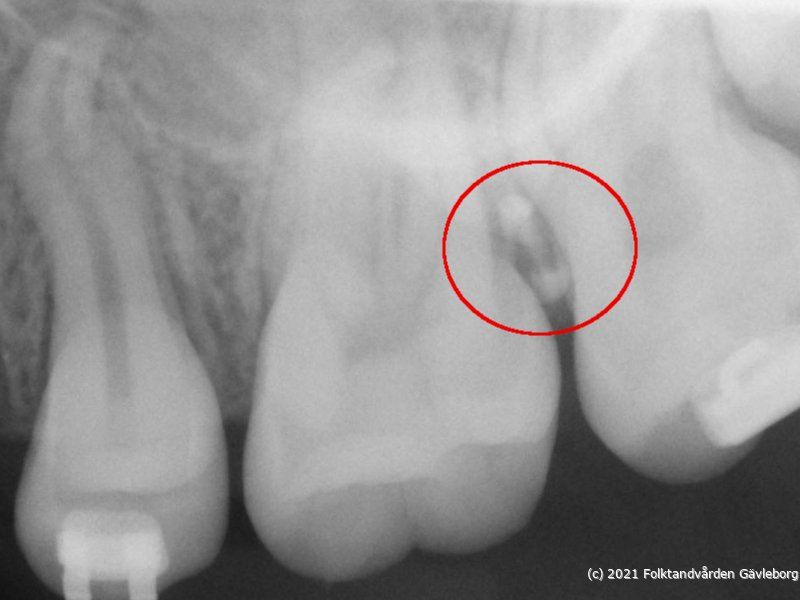

• sep03Fel placering!